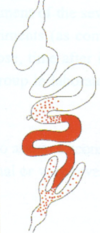

Leishmania sp.: Life cycle

Passed on by the saliva (not faeces)

Leishmania sp.: Form type In vertebrates

Amastigotes

Leishmania sp.: Form type In insects

Promastigotes

Leishmania sp.: Vector

Female sand fly